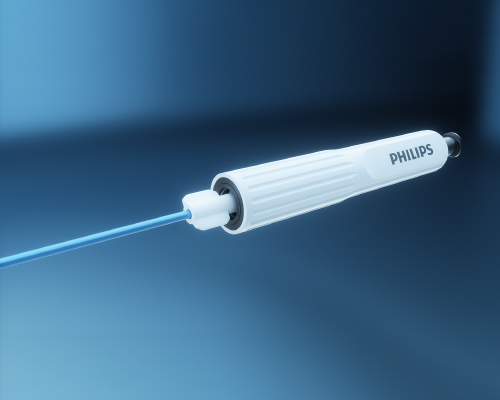

Fiber Optic RealShape (FORS) technology

Using light instead of X- ray

Device visualization using the wonders of light

With FORS technology, clinicians can carry out parts of minimally-invasive interventions without the need for X- ray, which should minimize the risks associated with long-term radiation exposure.

- How does Fiber Optic RealShape technology work?

-

A four-core optical fiber is integrated into a guidewire. By sending light into this fiber and then analyzing how the light is reflected back along the length of the fiber, it becomes possible to calculate the shape as well as the perspective. In fact, you can ‘see’ the whole fiber, and thereby the guidewire (and a catheter slid over it). In real time. There is no need for additional external imaging technology; the device literally visualizes itself.